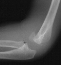

- XRAYS: Radiographic examination of the right upper extremity revealed

a displaced fracture involving the lateral condylar physis exiting through

the substance of the capitellum.